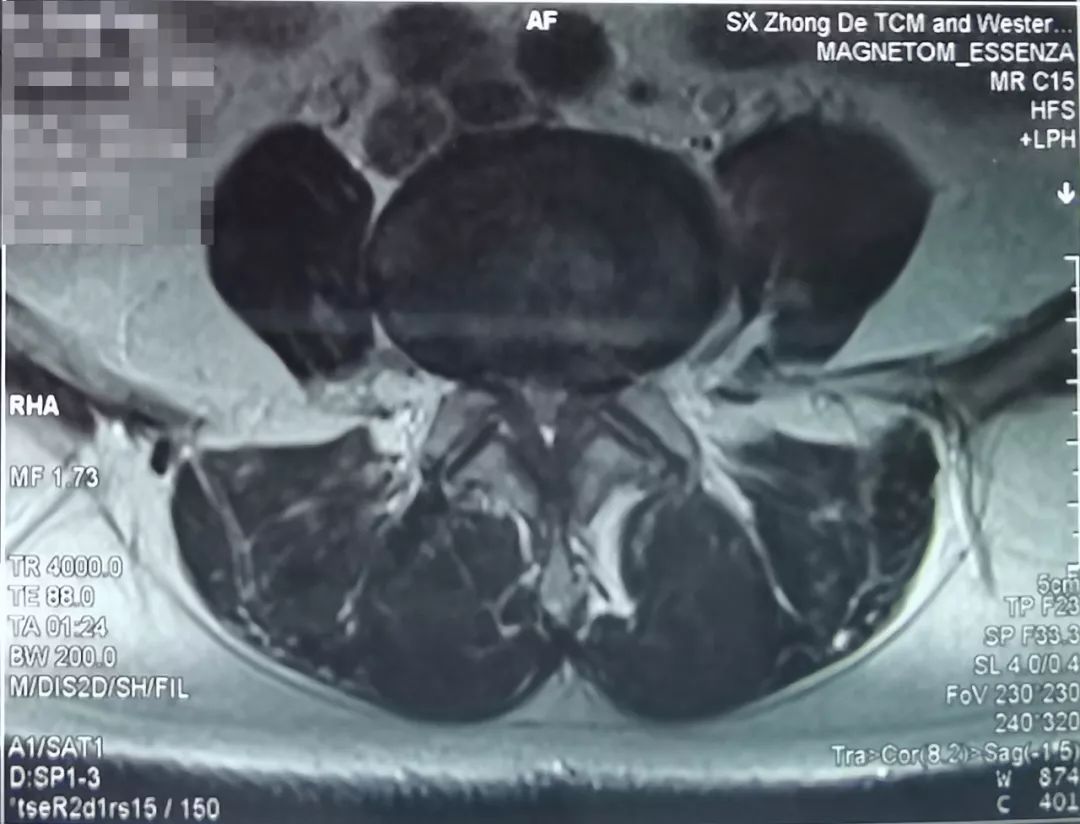

患者,女,63岁,主诉近期腰疼,双腿抽痛、麻木。之前在当地医院保守治疗1个月,效果不明显。

了解患者病情及影像学资料、仔细查体后,空军军医大学唐都医院骨科脊柱病区李晓祥博士诊断患者为腰椎间盘突出症、腰椎管狭窄症,并建议进行微创手术治疗。

像上面这样的患者出现症状影响生活,并且从影像学资料上看突出造成严重的腰椎管狭窄,已经压迫到神经,经过保守治疗后效果不好,这种情况就能够斟酌手术治疗。